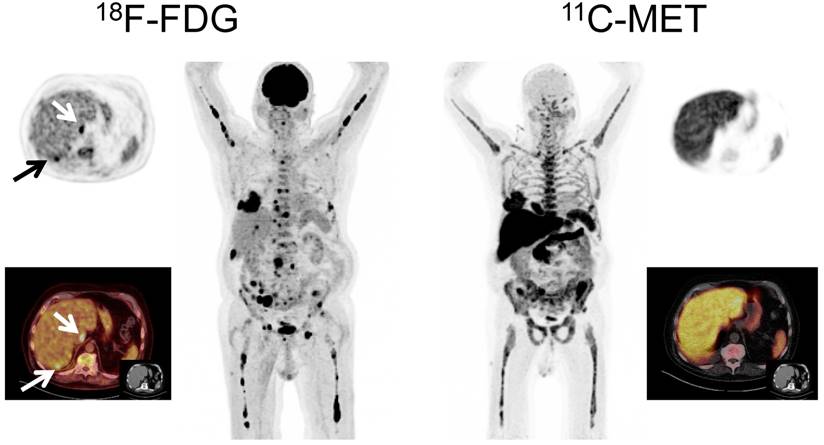

PET-directed biopsies and histopathological assessment

In order to confirm the specificity of MET-PET, directed histopathological biopsies were performed in two patients with discordant results between FDG-PET and MET-PET. In one case with FDG+ and MET- imaging (patient # 67, Figure 4), the guided biopsy did not show plasma cell infiltration whereas in the second case (MET+/FDG-, patient # 62, Figure 5), infiltration of clonal plasma cells was confirmed. Accordingly, in both cases the biopsy results were concordant with the MET-PET findings.

Figure 4

Display of a patient (patient #71) with a history of Ig G κ MM after treatment initiation with lenalidomide and dexamethasone. The patient was referred for further evaluation of a painful, growing lesion in the proximal third of the right clavicle. The lesion demonstrated focal FDG uptake. In contrast, MET-PET was negative (arrows). Biopsy was performed and no tumor infiltration was demonstrated, consistent with a benign fracture. MET-PET additionally revealed partial response with inhomogeneous, focally increased tracer uptake of the axial as well as appendicular skeleton, whereas FDG-PET did not depict hypermetabolic foci suspicious for active MM in these locations.

Figure 5

Display of a patient (patient #3) with a history of solitary plasmacytoma treated with radiotherapy. Imaging with both tracers was performed on the same day. Whereas PET/CT with FDG did not depict hypermetabolic foci suspicious for active MM, MET demonstrated focally increased tracer uptake in the left zygomatic bone (arrows). Biopsy confirmed monoclonal plasma cell infiltration.